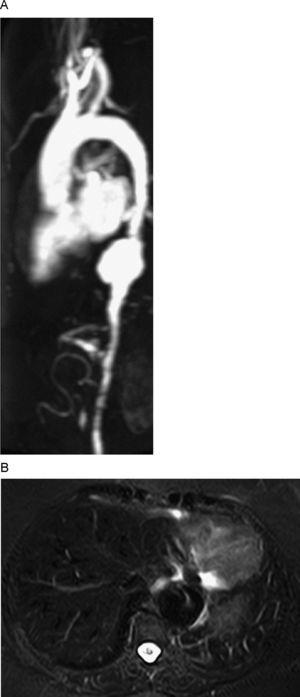

Las técnicas de imagen desempeñan un papel fundamental en el diagnóstico y monitorización de la vasculitis de vasos grandes. La arteritis de Takayasu afecta principalmente a mujeres jóvenes, en la zona de la aorta torácica y abdominal así como a sus ramas y a las arterias pulmonares. Presentan típicamente oclusión o estenosis proximal de las arterias subclavias y carótidas comunes. Hasta en un 33% de los pacientes se forman aneurismas aórticos, que raramente se rompen (fig. 1A)6. Con frecuencia la angiografía convencional es normal en las formas de inicio (fase sin pérdida de pulso), no se establece habitualmente el diagnóstico hasta que se produce estenosis (fase oclusiva)8. Las alteraciones inflamatorias en la pared de los vasos afectados son un signo precoz que puede ser detectado mediante ecografía, TC, RM y PET3. Para el análisis de la aorta es preferible utilizar técnicas angiográficas con TC o RM (que es la técnica más sensible para la detección del edema) (fig. 1B)9. La PET ha demostrado una sensibilidad similar a la RM en la detección de la enfermedad, en la que descubre más segmentos afectados que ésta10. La arteritis de células gigantes es otra vasculitis granulomatosa de vasos grandes, que afecta principalmente a las ramas craneales del arco aórtico, particularmente a la arteria temporal. En la evaluación de la arteritis de la arteria temporal, la ecografía Doppler ha demostrado tener sensibilidades en torno al 85 o 90% y ha demostrado especificidades superiores al 95%, resultados comparables o superiores a la biopsia de la arteria temporal3,4. La RM también puede evaluar las arterias temporales y occipitales con resultados similares a los de la ecografía11. La afectación aórtica y de los vasos supraaórticos puede realizarse por ecografía, TC, RM o PET de forma similar a la arteritis de Takayasu3.

Figura 1. Mujer de 59 años con enfermedad de Takayasu. A) Reconstrucción MIP sagital de secuencia angiográfica 3D poscontraste de la aorta toracoabdominal. Demuestra un aneurisma de la aorta torácica descendente distal. Estenosis y morfología tubular de la aorta torácica descendente y de la abdominal y estenosis en la salida de la arteria subclavia izquierda, tronco celíaco y arteria mesentérica superior. B) Axial STIR sangre negra demuestra un aneurisma de aorta torácica distal con edema parietal que aparece como hiperintensidad de señal.